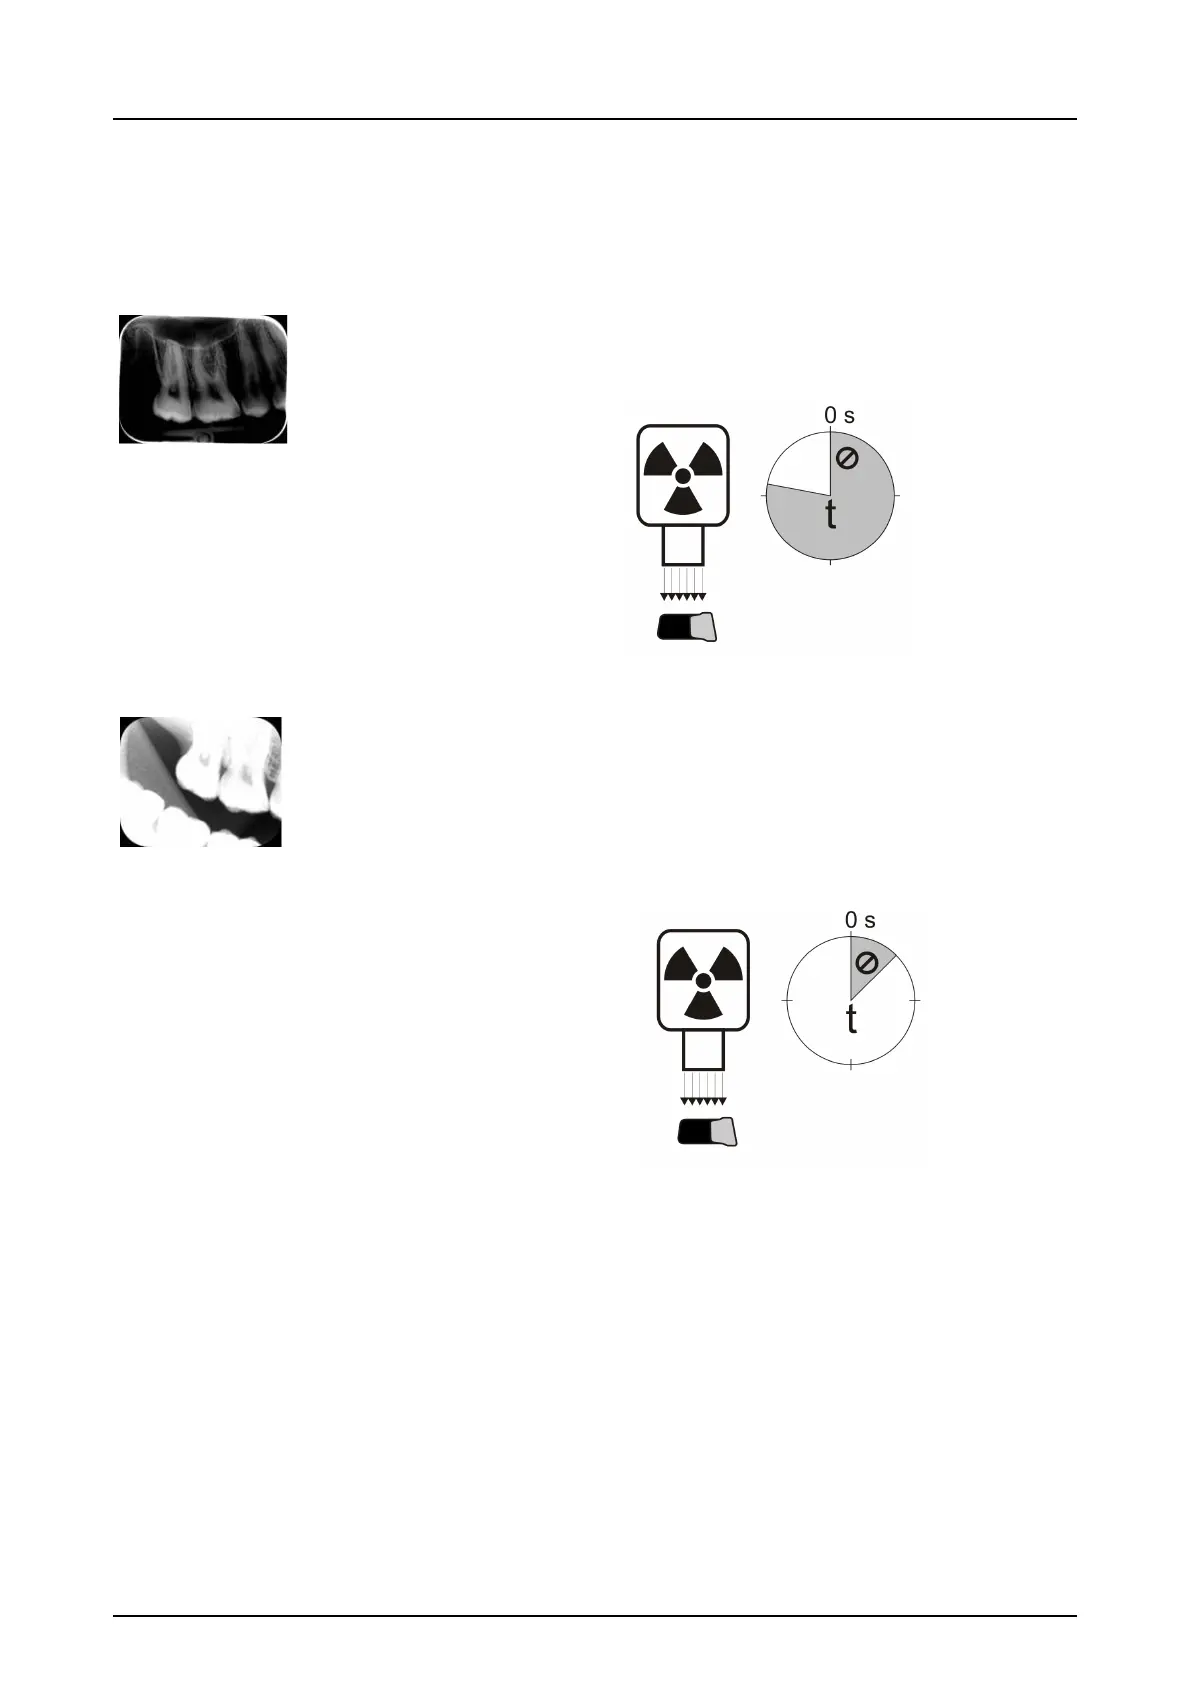

Improper x-ray settings used

Too dark image. Some areas showing uniform “black”.

Decreased diagnostic value.

Too long exposure time/too high X-ray dose.

Too light, noisy image with decreased diagnostic value.

Showing only part of the image.

Showing wrong size of the image (Image smaller than

imaging plate).

Too short exposure time / Too low X-ray dose.